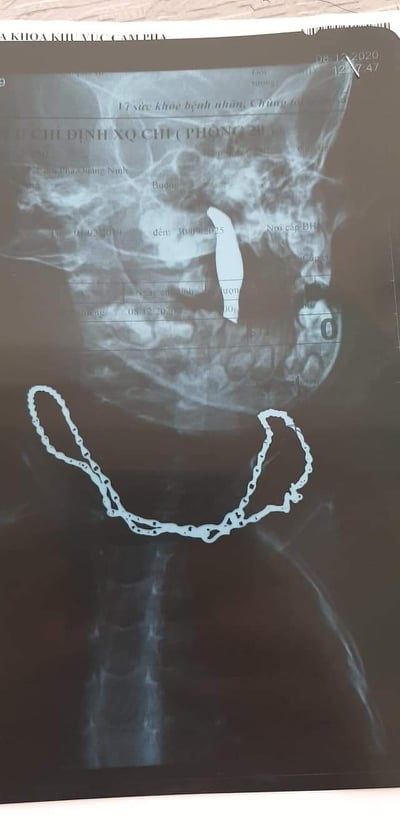

Quảng Ninh: Phẫu thuật lấy ra khỏi hàm bệnh nhi 01 cây nhíp bằng thép dài 10 cm xuyên từ miệng lên mũi

Các bác sĩ lấy ra khỏi hàm bệnh nhi 01 cây nhíp bằng thép dài 10 cm.

Ngày 11/12, trao đổi thông tin với PV Pháp luật Plus, BS Nguyễn Đức Thanh, Giám đốc Bệnh viện Đa khoa Khu vực Cẩm Phả, tỉnh Quảng Ninh cho biết, vừa qua khoa Tai Mũi Họng của đơn vị này đã tiếp nhận bệnh nhi là bé trai Nguyễn Q.C,( 1 tuổi, trú tại Phường Cửa Ông, TP Cẩm Phả, tỉnh Quảng Ninh) nhập viện trong tình trạng quấy khóc, vùng hàm họng chảy máu nhiều.

Kết quả chẩn đoán hình ảnh và thăm khám cho thấy bệnh nhi có dị vật dạng sắt dài khoảng 10 cm cắm xuyên thủng từ vòm khẩu cái lên sàn mũi, vết thương rỉ nhiều máu chảy xuống họng, đầu ngoài dị vật còn nhô ra khoảng 5cm nằm toàn bộ trong khoang miệng.

Cây nhíp được lấy ra khỏi vùng hàm bệnh nhân.

Các bác sỹ nhận định đây là ca bệnh dị vật vùng hàm mặt- họng phức tạp, cần phẫu thuật lấy dị vật ngay. Ca phẫu thuật thành công, các bác sĩ lấy ra khỏi hàm bệnh nhi 01 cây nhíp bằng thép dài 10 cm.

Sau phẫu thuật, bệnh nhi hết chảy máu, hồi phục tốt. Qua ca bệnh này, BS Thanh khuyến cáo, gia đình có trẻ nhỏ cần luôn chú ý, quan sát trẻ trong lúc trẻ vui chơi; ngăn chặn kịp thời khi trẻ sử dụng hoặc cầm chơi các đồ chơi hoặc những vật dụng sinh hoạt thường ngày có kết cấu cứng, hình dạng dài nhọn dễ gây tổn thương cho trẻ: que tăm, đinh nhọn, đũa, dĩa...